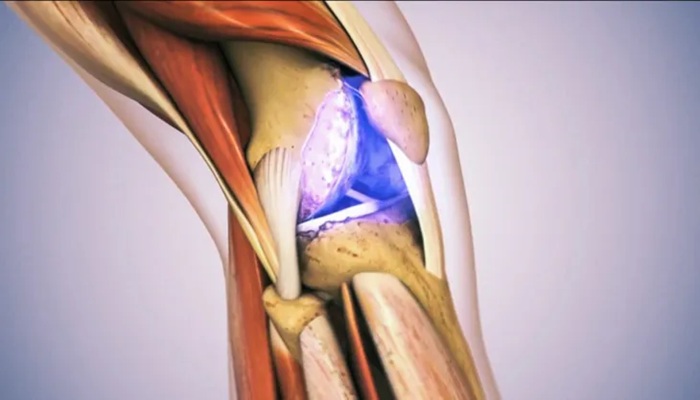

من الناحية الفسيولوجية، يُعد الغضروف الذي يغطي أطراف العظام طبقة واقية لا تحتوي على إمدادات دم خاصة. ويؤدي الضغط عليه أثناء المشي أو الحركة إلى إخراج السوائل منه، ما يسمح بتجديد العناصر الغذائية والمزلقات الطبيعية داخل المفصل، وهو ما يُسهم في الحفاظ على صحته.

بالتالي، فإن الاعتقاد السائد بأن الفصال العظمي ناتج عن "تآكل طبيعي" للمفاصل هو فهم غير دقيق. فالمفاصل لا "تستهلك" مثل إطارات السيارات، بل تمر بعمليات مستمرة من التآكل والإصلاح، تجعل الحركة والتمارين المنتظمة ضرورية لشفائها.